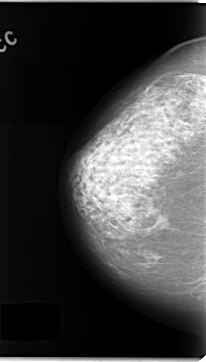

C_0144_1.LEFT_CC

FILE: C_0144_1.LEFT_CC.OVERLAY

TOTAL_ABNORMALITIES 1

ABNORMALITY 1

LESION_TYPE CALCIFICATION TYPE FINE_LINEAR_BRANCHING DISTRIBUTION REGIONAL

ASSESSMENT 5

SUBTLETY 5

PATHOLOGY MALIGNANT

TOTAL_OUTLINES 1

BOUNDARY